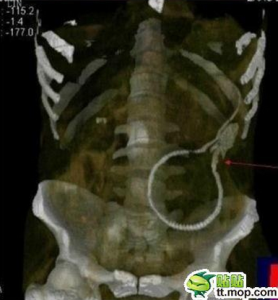

According to the doctor, the 20″ eel gnawed its way through the man’s

colon into his body, causing massive internal bleeding. The man

underwent emergency surgery and miraculously survived. Surprisingly, his

One Japanese website that

reported the incident explained where the eel was positioned when

doctors eagerly worked to get it out of the man. The site, which had to

be translated in English, reports: “Yesterday, Foshan, a female

doctor microblogging explosion metamorphosis incident, a man playing the

eel burst chrysanthemum, results of a pound weight of the eel got into

the large intestine, causing intestinal perforation, the surgeon in the

hospital with a one night only then eel caught out. Posts with eel

picture. The eel huddled mass lying on the iron plate, the next b****y

gauze, eel body length of about 50cm.” In other words, the eel was lying on the man’s iron plate when surgeons took him/her out.